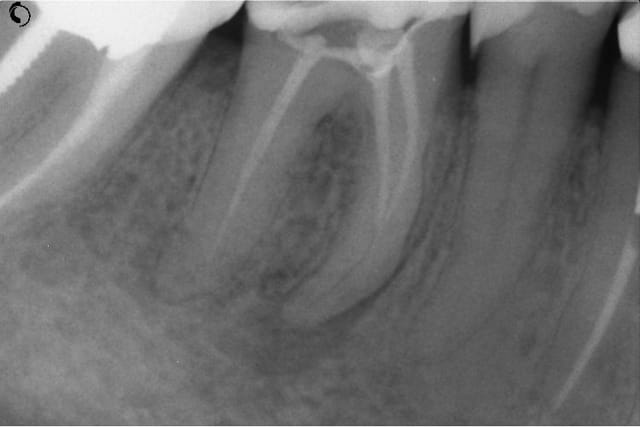

NB: ne pas chipoter svp sur l'appellation "kyste"

Kyste1 xpgssa - Eugenol

Kyste2 sef5wb - Eugenol

Repriseinit tk8kzi - Eugenol

Reprise4cx uandde - Eugenol